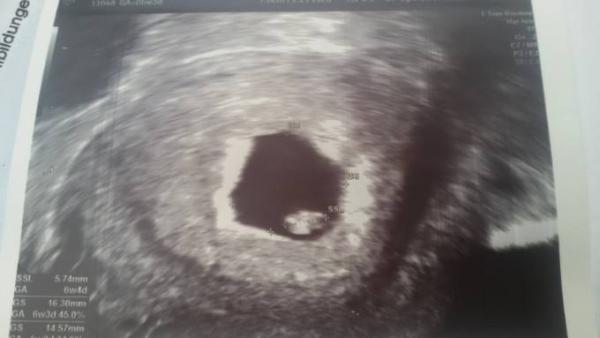

Hallo Liebe Muttis , Also ich bin aktuell in der 7. Fast 8. Woche. Ich hatte gestern meinen ersten regulären Termin . Wurde aufgeklärt über die üblichen Sachen und ein Ultraschall wurde gemacht . Bild hängt an ;-) Es ist alles in der Norm . Vor 14 Tagen war ich wegen starker Schmerzen schon mal . Da hat man nur eine Erbsengroße Fruchthöhle gesehen . So nun habe ich in vier Wochen , am 3.5. Wieder Termin . Dort wird dann auch Blut abgenommen und dann gehe ich zur Hebamme ( die ist direkt mit in der Praxis ) mein Großer ist 6 jahre alt . Bei um war ich damals das erste mal in der 9. Woche und bekam da alle Untersuchungen und Mutterpass. ich finde das irgendwie komisch . Das die sich so viel Zeit lassen mit dem Blutbild. Und dem Mutterpass. Ich mein, man hat das Herz schlagen sehen . Warum dann noch keinen Mutterpass . Finde ich blöd. Ist das ok so ?

Bild zu Termine beim Frauenarzt . Mutterpass erst in 11. Woche ? mit Bild :-) - Forum für November - Mamis